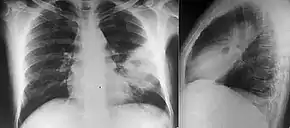

People with diabetes mellitus or regular exposure to the bacteria are at increased risk of developing melioidosis. The disease should be considered in those staying in endemic areas who develop fever, pneumonia, or abscesses in their liver, spleen, prostate, or parotid glands.[1] The clinical manifestation of the disease can range from simple skin changes to severe organ problems.[1] Skin changes can be nonspecific abscesses or ulcerations.[6] In northern Australia, 60% of the infected children presented with only skin lesions, while 20% presented with pneumonia.[3] The commonest organs affected are liver, spleen, lungs, prostate, and kidneys. Among the most common clinical signs are presence of bacteria in blood (in 40 to 60% of cases), pneumonia (50%), and septic shock (20%).[1] People with only pneumonia may have a prominent cough with sputum and shortness of breath. However, those with septic shock together with pneumonia may have minimal coughing.[2] Results of a chest X-ray can range from diffuse nodular infiltrates in those with septic shock to progressive solidification of the lungs in the upper lobes for those with pneumonia only. Excess fluid in the pleural cavity and gathering of pus within a cavity are more common for melioidosis affecting lower lobes of the lungs.[2] In 10% of cases, people develop secondary pneumonia caused by other bacteria after the primary infection.[3]

Various imaging modalities can also help with the diagnosis of melioidosis. In acute melioidosis with the spreading of the bacteria through the bloodstream, the chest X-ray shows multifocal nodular lesions. It may also show merging nodules or cavitations. For those with acute melioidosis without the spread to the bloodstream, chest X-ray shows upper-lobe consolidation or cavitations. In chronic melioidosis, the slow progression of upper-lobe consolidation of the lungs resembles tuberculosis. For abscesses located in other parts of the body apart from the lungs, especially in the liver and spleen, CT scan has higher sensitivity when compared with an ultrasound scan. In liver and splenic abscesses, an ultrasound scan shows "target-like" lesions, while CT scan shows "honeycomb sign" in liver abscesses. For melioidosis involving the brain, MRI has higher sensitivity than a CT scan in diagnosing the lesion. MRI shows ring-enhancing lesions for brain melioidosis.[7]